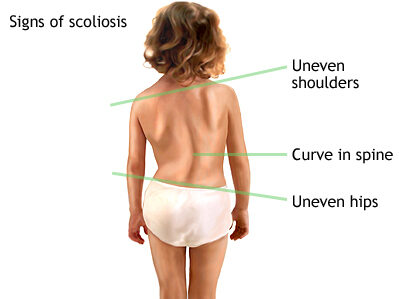

علامات اعوجاج العمود الفقري التحذيرية: 7 علامات مبكرة يجب أن يعرفها كل أب وأم يتساءل كثير من الآباء والأمهات: ما هي العلامات التحذيرية لاعوجاج العمود الفقري؟ وهل يمكن اكتشاف المشكلة مبكرًا قبل أن تزداد